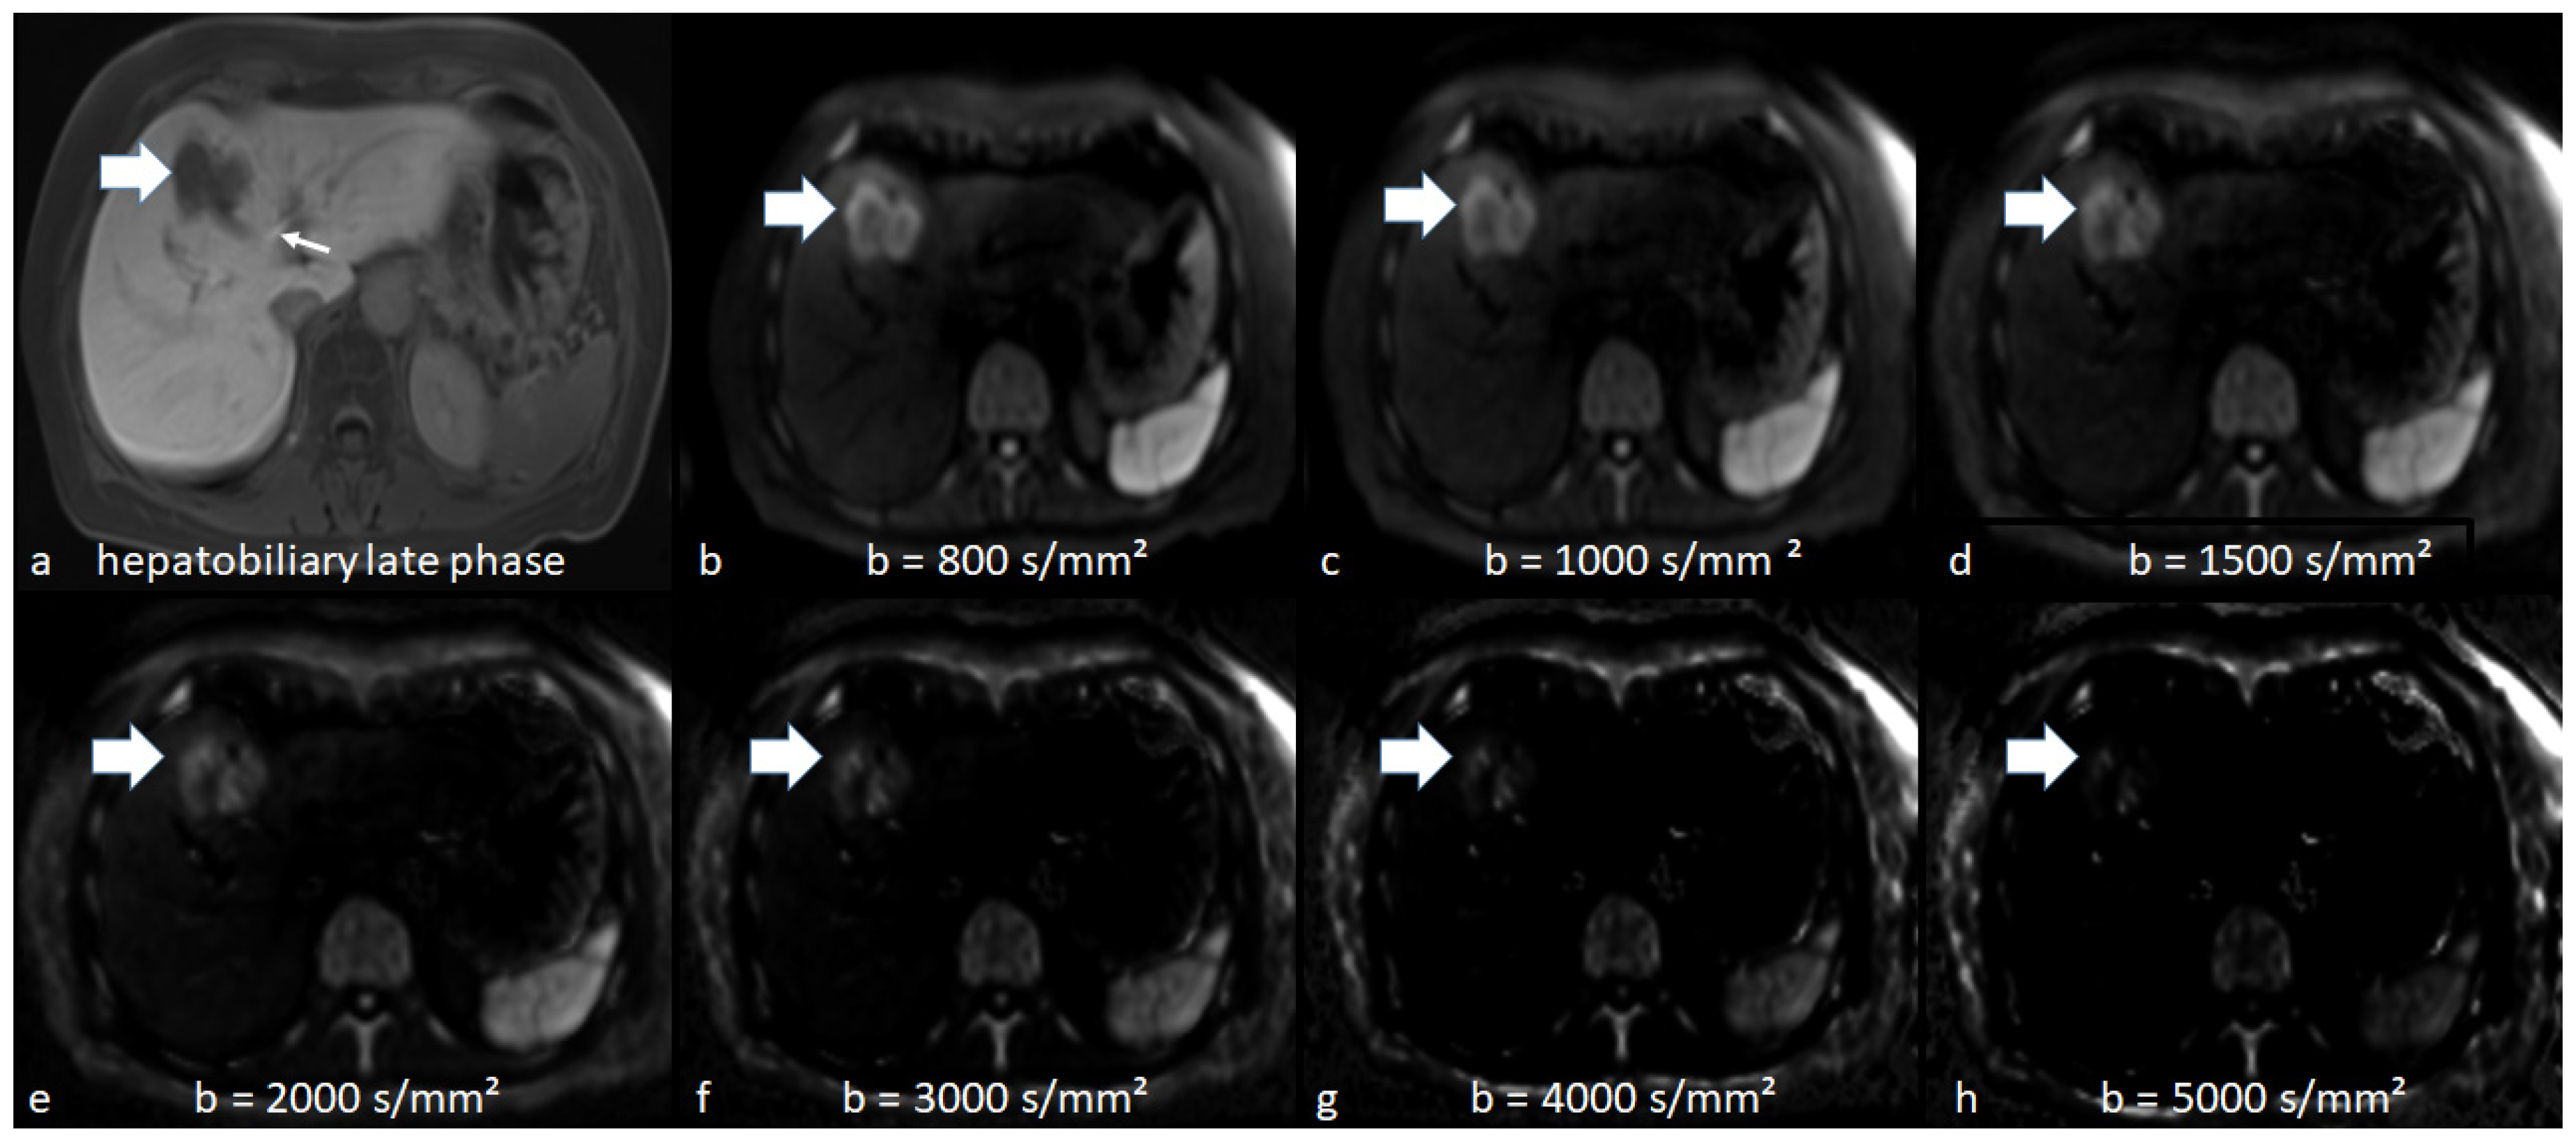

3.2. Qualitative Analysis